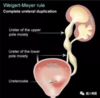

What does the Weigert-Meyer rule predict re: the upper pole moiety?

It will insert inferior and medial.